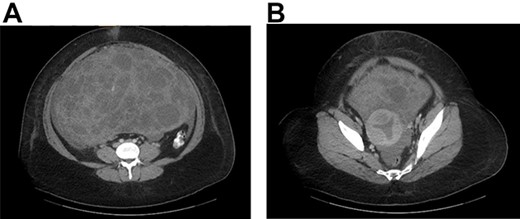

On examination, she was hemodynamically stable. Abdomen was distended and tender to palpation. A fluid shift was present. Computed tomography (CT) abdomen and pelvis demonstrated a 29 × 19-cm pelviabdominal mass with significant ascites. The mass contained both cystic and solid components as well as internal vascularity (Fig. 1A and 1B).

(A) CT abdomen and pelvis with contrast identified a large pelviabdominal mass with internal vascularity measuring 29 × 19 cm and significant ascites; the mass contained both cystic and solid components. (B) The mass encasing the uterus.